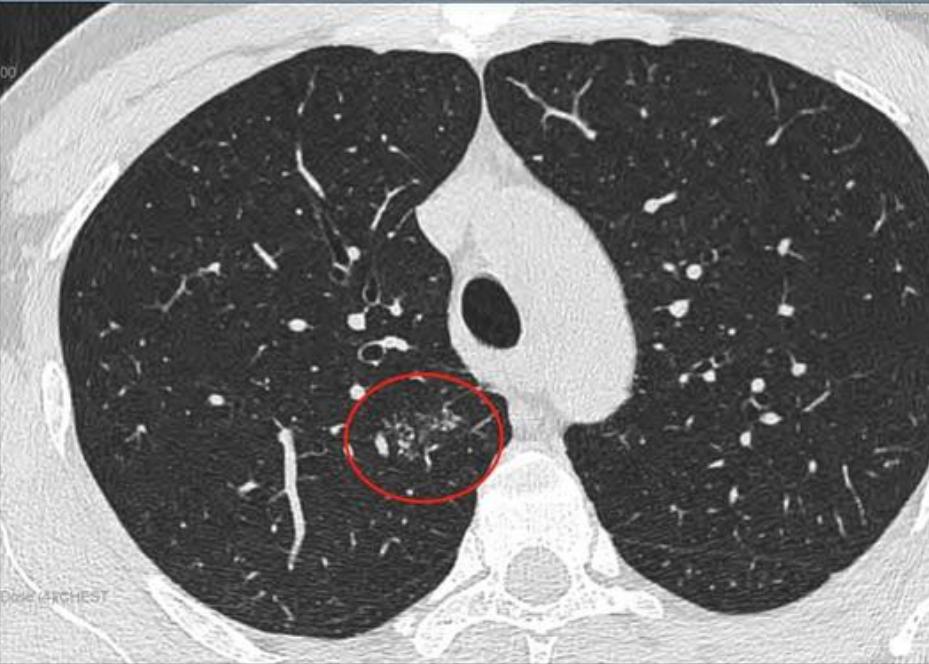

这是11月15日的CT图像与上次(7月29日)CT图像对比图:

再发一张:

辛苦主任,您看一下,结节虽然缩小了,还有1.7*0.9 CM,其他俩肺叶还有陈旧性病灶,应该继续服用拜复乐和夏枯草吗?8月份查过:男性肿标9项、过敏源检测(总IgE)、鳞状上皮细胞癌相关抗原、GM试验、隐球菌抗原、1,3-β-D葡聚糖 都是阴性,在正常范围内。就是结核感染T细胞还没查,您看是否需要查一下?主任辛苦您了,谢谢您!